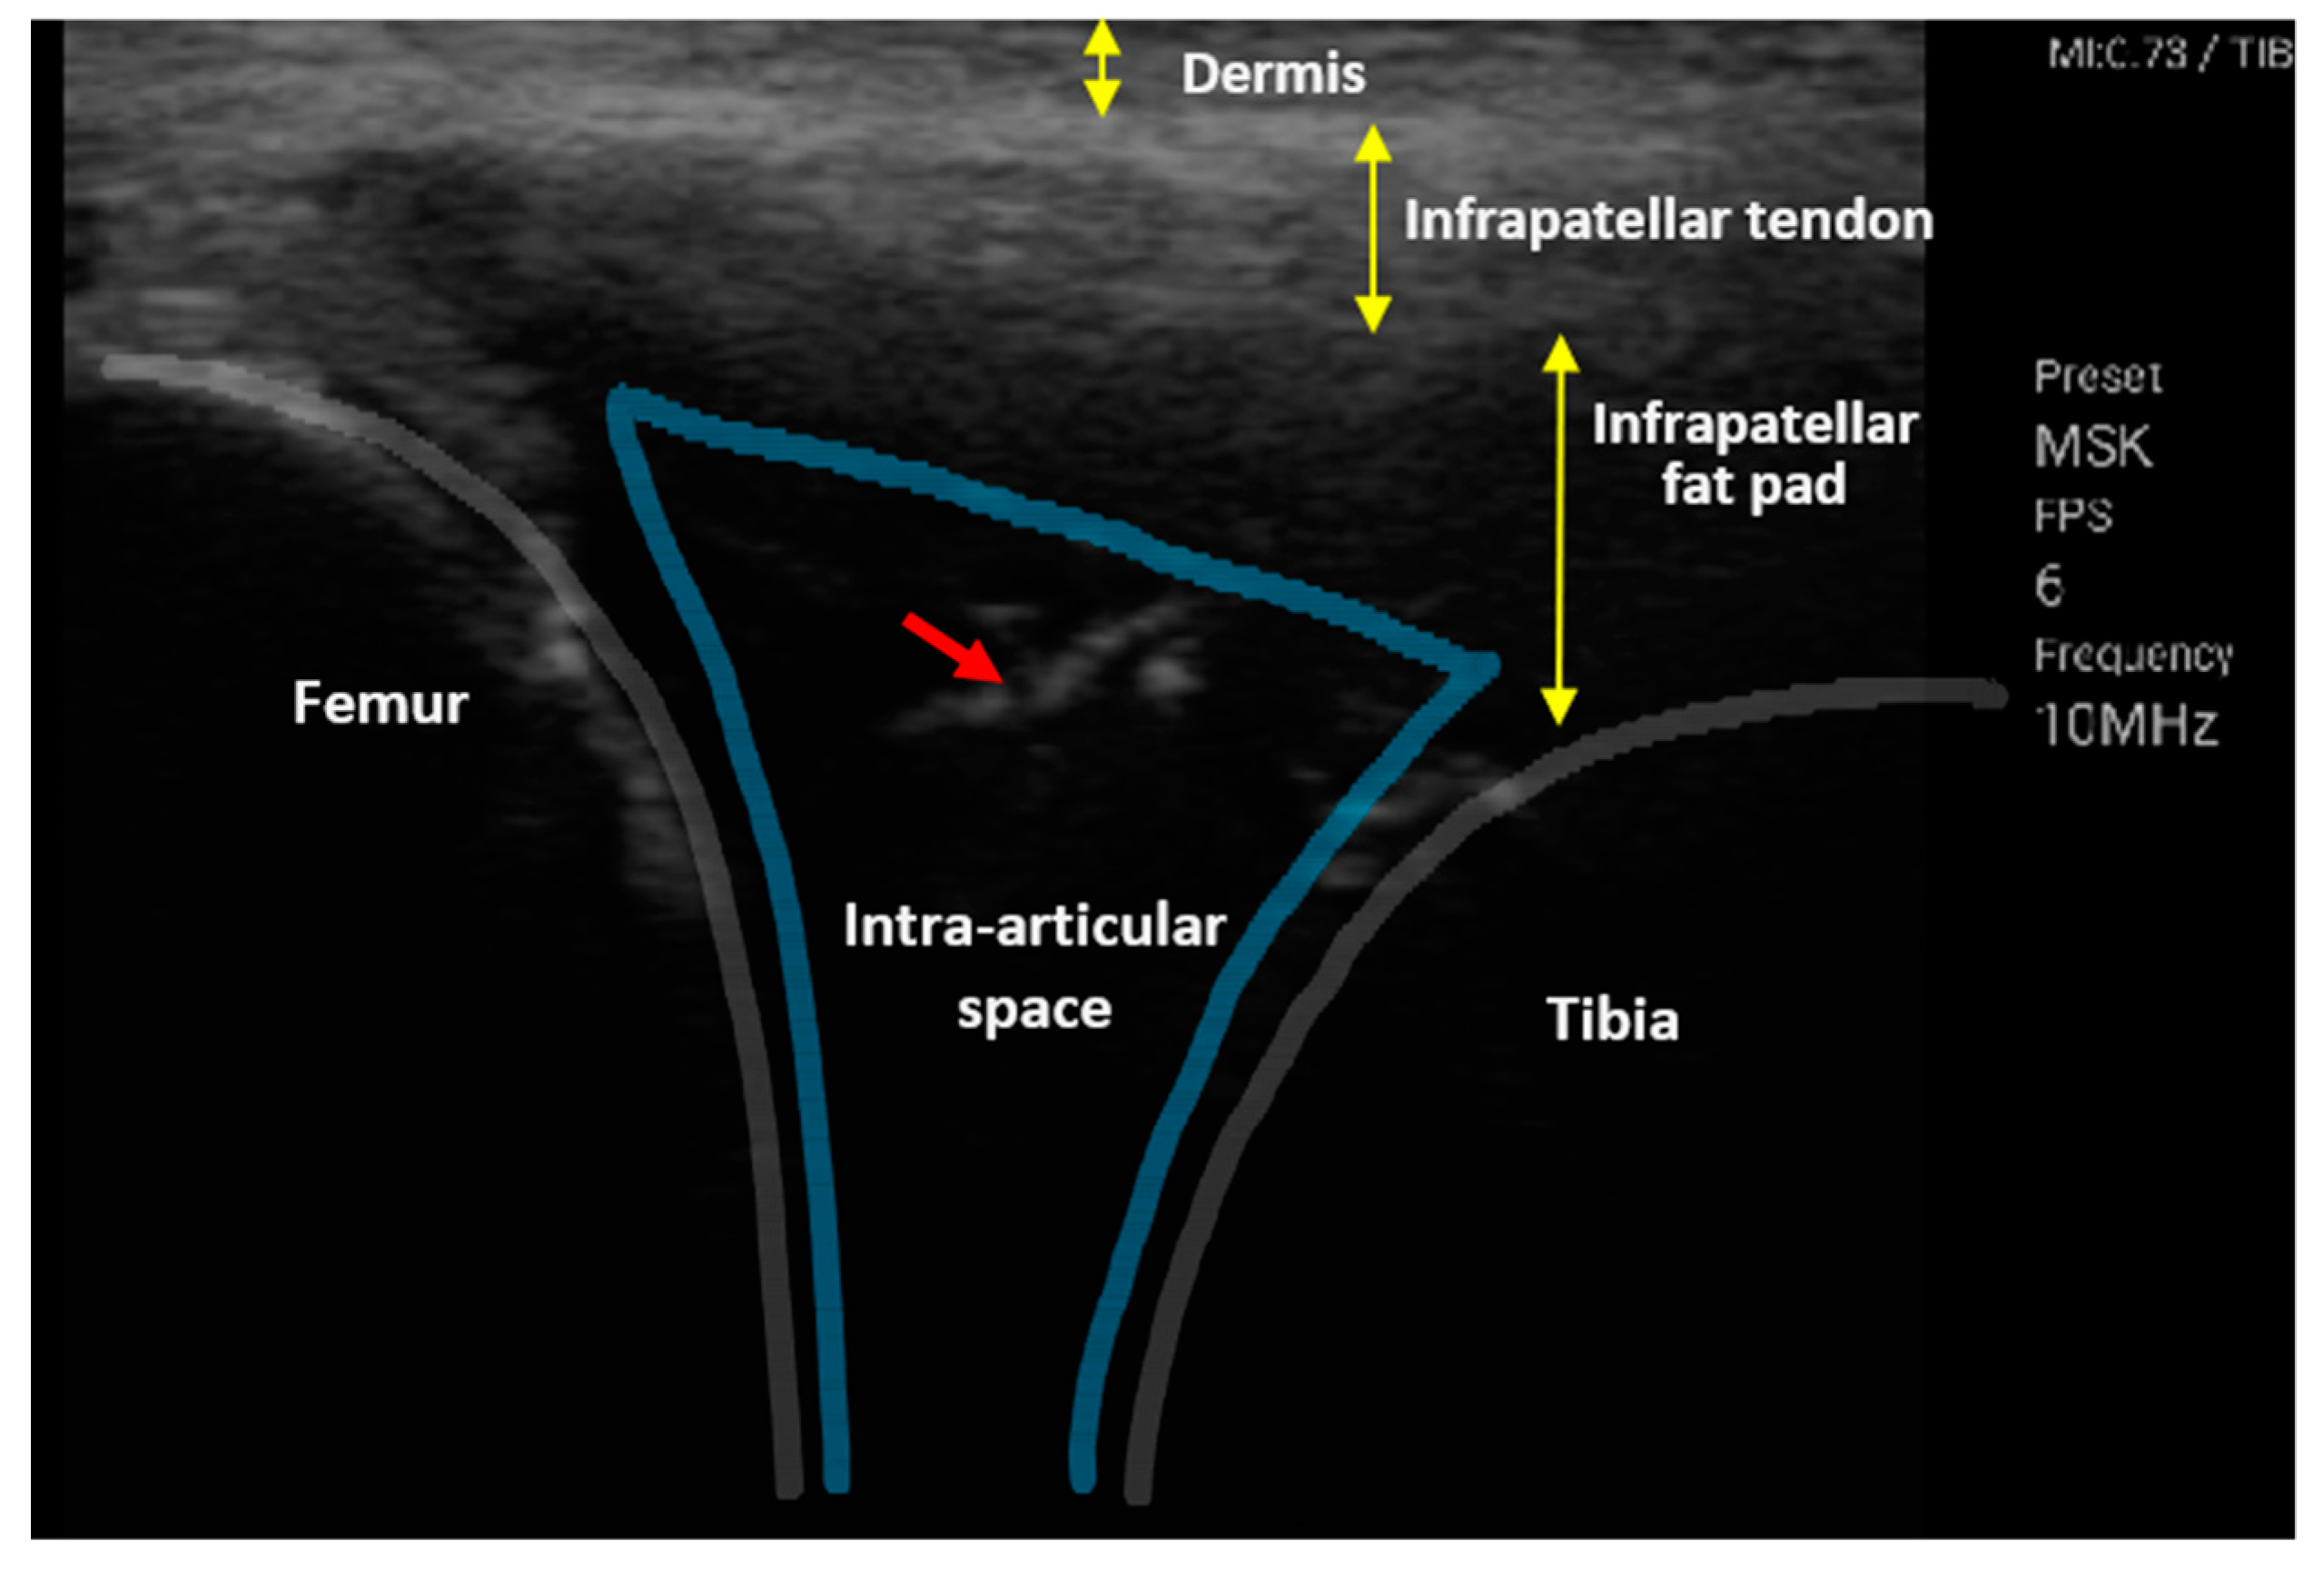

2.2. Experimental Setup

3.3. Impedance Monitoring of the Needle Tip in the Intra-Articular Cavity